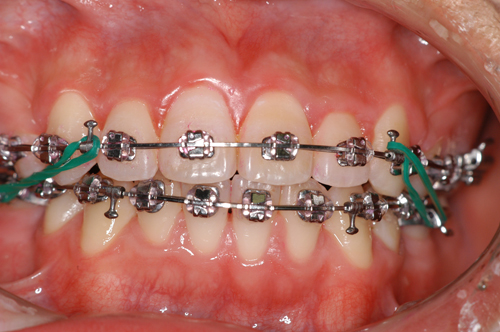

患者:14歳8ヶ月 男性

抜歯部位:上顎、第一小臼歯 下顎第二小臼歯

動的治療期間:18ヶ月